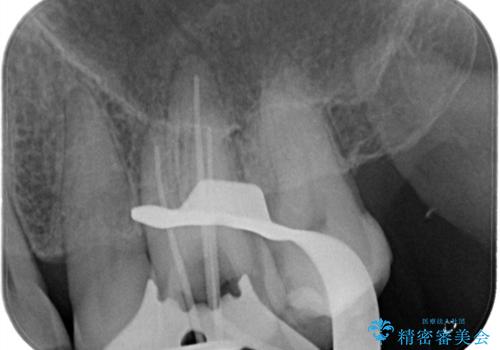

根管治療にはラバーダムシートをつけて行うことが大切です。マイクロスコープを使用し治療を行いました。治療後、歯の痛みは消失し、とても満足していただきました。

根管治療を行った歯は、再発防止や残された歯質を守るため、クラウンによる補綴治療が必要となります。